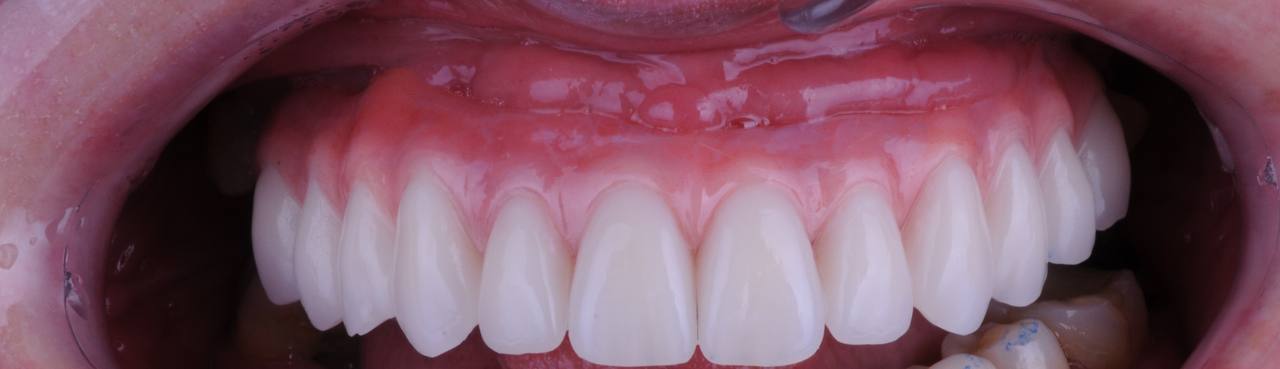

Завершающий ортопедический этап – несъемный циркониевый протез на 6 имплантах верхней челюсти и виниры на нижней